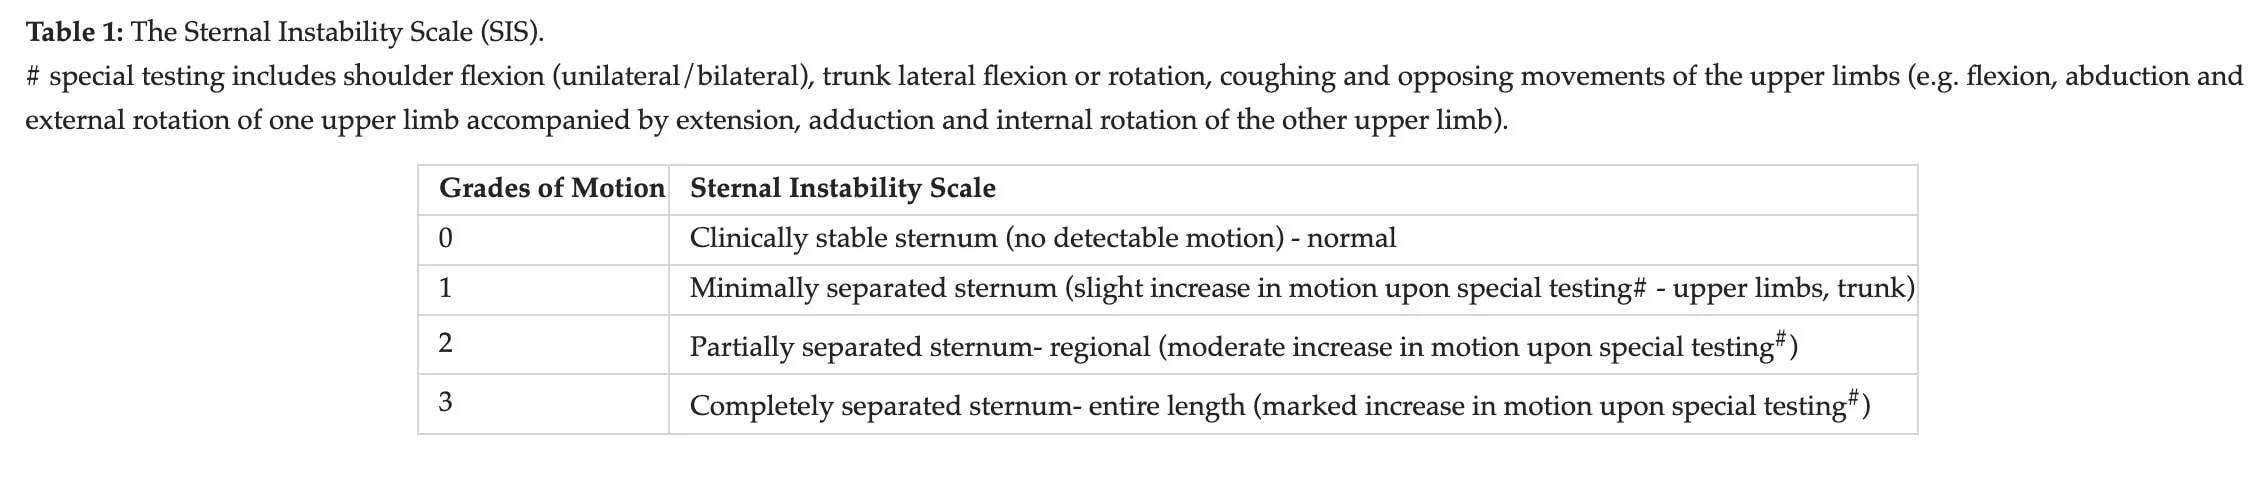

主要结果是使用超声波测量胸骨分离度。 对两半胸骨之间的距离进行量化,并标记出最大分离点。 作为次要结果,胸骨不稳定性量表用于评估从0级(胸骨临床稳定)到3级(胸骨大幅移动或分离)的胸骨完整性。 测量在基线(术后第 7 天)和第 4 周进行。

次要结果支持主要分析,但置信区间更宽。 因此,胸骨不稳定性量表的结果具有更大的不确定性。 一些参与者有了明显改善,而另一些则改善甚微。 不过,胸骨不稳定性量表是一种主观测量方法,因为它是在体格检查时评估胸骨的移动程度。 然而,这需要专业知识,而且要评估的运动量非常小,极易出现误差和研究人员的偏差。 这也许可以部分解释为什么这些研究结果的置信区间要大得多。 El-Ansary 等人(2000 年)报告称,经过培训和标准化检查程序后,评分者之间(99%)和评分者内部(98%)的可靠性达到了完美水平。 不过,这项研究的主观性以及对这种细微动作的触诊可能需要进一步验证。